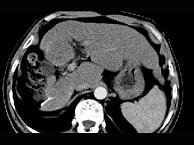

问题 女性,56岁,腹胀、双下肢水肿、乏力、食欲不振,影像所见如下图,最佳的诊断是 ( )

选项 A.酒精性肝硬化并肝血管瘤 B.血吸虫肝硬化并肝癌 C.肝炎后肝硬化并肝癌 D.局限性脂肪肝 E.原发性肝癌

答案 B